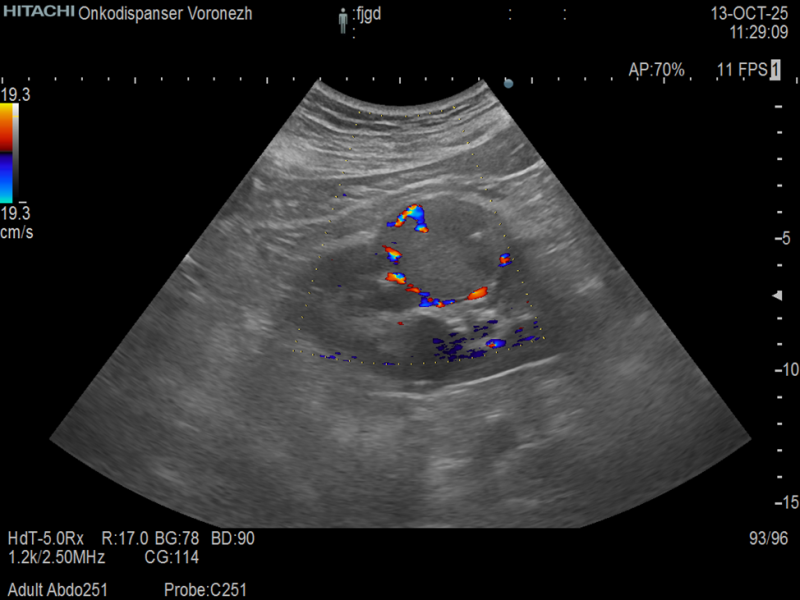

• как случайная находка при диспансерном проведении ультразвукового исследования (УЗИ), компьютерной (КТ) и магнитно-резонансной (МРТ) томографий;

• как случайная находка при поиске неурологического заболевания (например, если при КТ легких в срез попал верхний сегмент почки с имеющейся опухолью; или когда выполняется УЗИ при желчекаменной болезни и выявляется опухоль правой почки);

• если наличие изменений в анализах крови и/или мочи послужило основанием к проведению УЗИ почек.